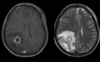

Name, characteristics, ring enhancing?

Glioblastoma multiforme

Pseudopallisading necrosis and microvascular proliferation

Ring enhancing - due to breakdown of BBB